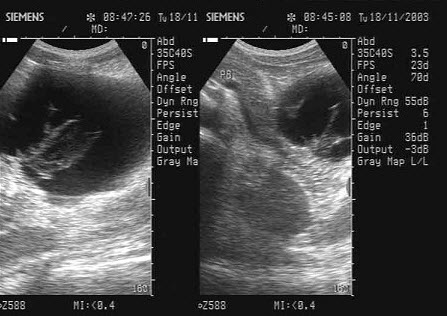

3、单项选择题

患者,女,42岁。3周前患急性胰腺炎,并给予治疗,现超声复查胰腺如图,诊断为()

A.急性胰腺炎

B.胰腺真性囊肿

C.胰腺假性囊肿

D.后腹膜肿瘤

E.胰腺囊腺癌